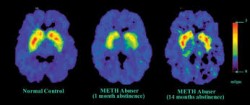

Addiction’s Effects on Brain Chemistry

Addiction can have a massive impact on brain functioning.

Frequent drug (or alcohol use) causes considerable damage to brain cell structures as well as brain cell functions. With each drug dose, brain cells work harder than normal to produce large amounts of neurotransmitter chemicals. These activities place a strain on cell structures, which inevitably start to deteriorate from overuse. As cell structures deteriorate, the brain becomes more dependent on drug effects to produce needed chemical supplies.